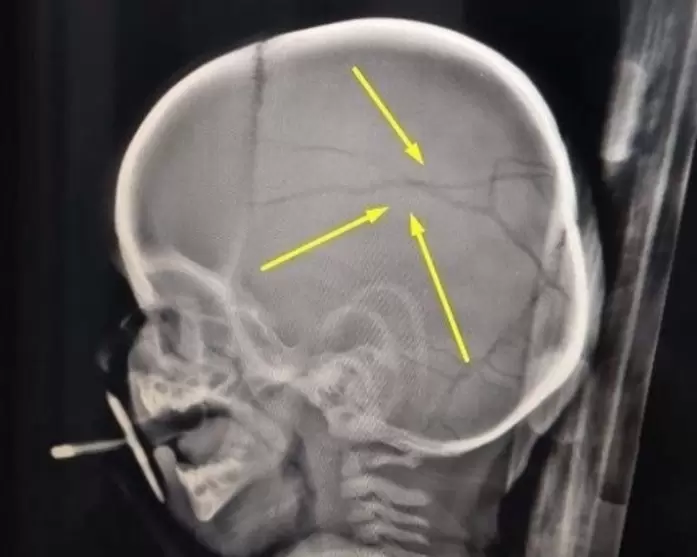

El horror sucedió en una casa de Coronel Suárez, sobre la avenida Independencia al 700, donde Roth fijó domicilio tras ser beneficiado con el régimen de "libertad asistida". Allí, según la denuncia, mantuvo cautiva durante tres días a su pareja de 19 años y a los dos hijos de ella: un nene de 3 años y el bebé de 11 meses. En ese encierro, la violencia escaló hasta lo inimaginable: el más pequeño terminó internado en el Hospital Penna de Bahía Blanca con múltiples fracturas en el cráneo.

El calvario se detuvo cuando, en un descuido del agresor, la joven logró escapar y pedir ayuda. Vecinos rescataron a los niños y la policía detuvo a Roth en la misma casa. Pero no era la primera vez y rápidamente las autoridades descubrieron que se trataba de un reincidente. En 2022, este mismo hombre había sido condenado a tres años y un mes de prisión por golpear brutalmente a una nena de dos años -la hija de otra expareja-, provocándole fractura de cráneo y lesiones compatibles con mordeduras. La nena quedó con secuelas en la vista. En aquel entonces, Roth intentó justificarse diciendo que la menor "se había caído". Los médicos comprobaron lo contrario.

Pese a ese antecedente, el juez Stemphelet consideró que merecía una segunda oportunidad. Basado en informes del Servicio Penitenciario que lo calificaban con "conducta ejemplar 10" y "concepto bueno", le concedió la libertad asistida. La condición era cumplir requisitos tan insólitos como ineficaces: abstenerse de consumir drogas y alcohol, someterse a controles, recibir asistencia psicológica y asistir a un curso titulado "Deconstruyendo masculinidades". Nada de eso lo detuvo. Hoy, Roth enfrenta una nueva causa por "tentativa de homicidio" en la UFIJ N° 15 de Bahía Blanca. Se negó a declarar. El bebé golpeado pelea por recuperarse en terapia intermedia.